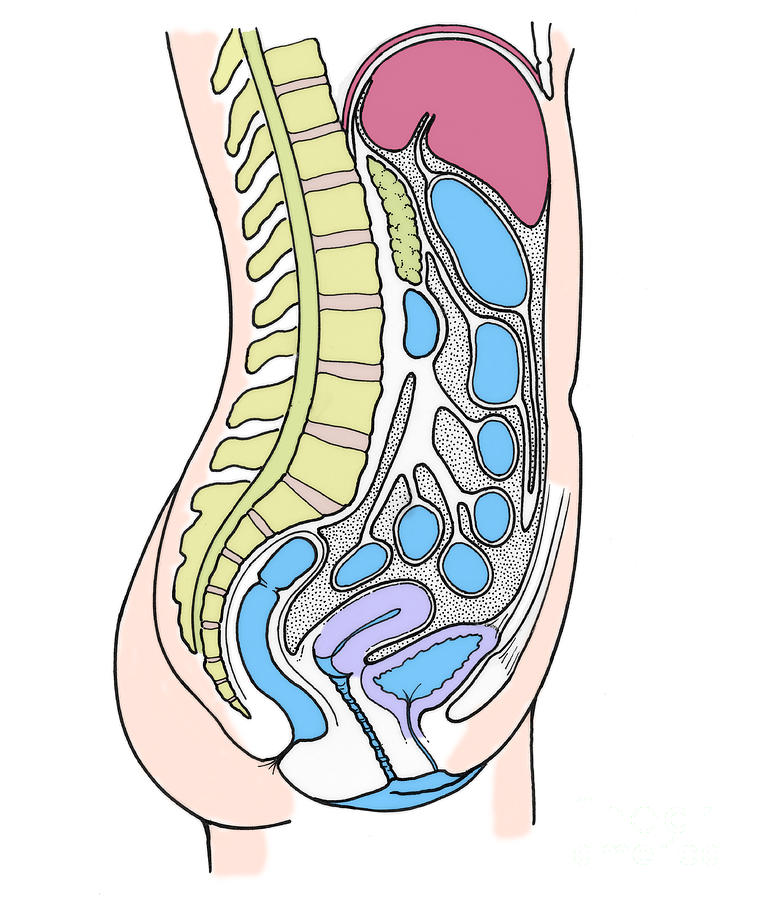

Female Abdominal Anatomy Images . Female Abdominal Anatomy Images …

Female Lower Back Anatomy Internal Organs : Bones of the Pelvis and …

Female Abdominal Anatomy Pictures – koibana.info | Anatomy organs …

Section Of Female Pelvic Organs Stock Photo – Download Image Now …

Abdominal and Pelvic Pain in the Nonpregnant Female | Tintinalli’s …

Stock Female Pelvis: Normal Anatomy — Illustrated Verdict

Female Abdominal Pain | Types | Symptoms | Causes | Diagnosis | Treatment